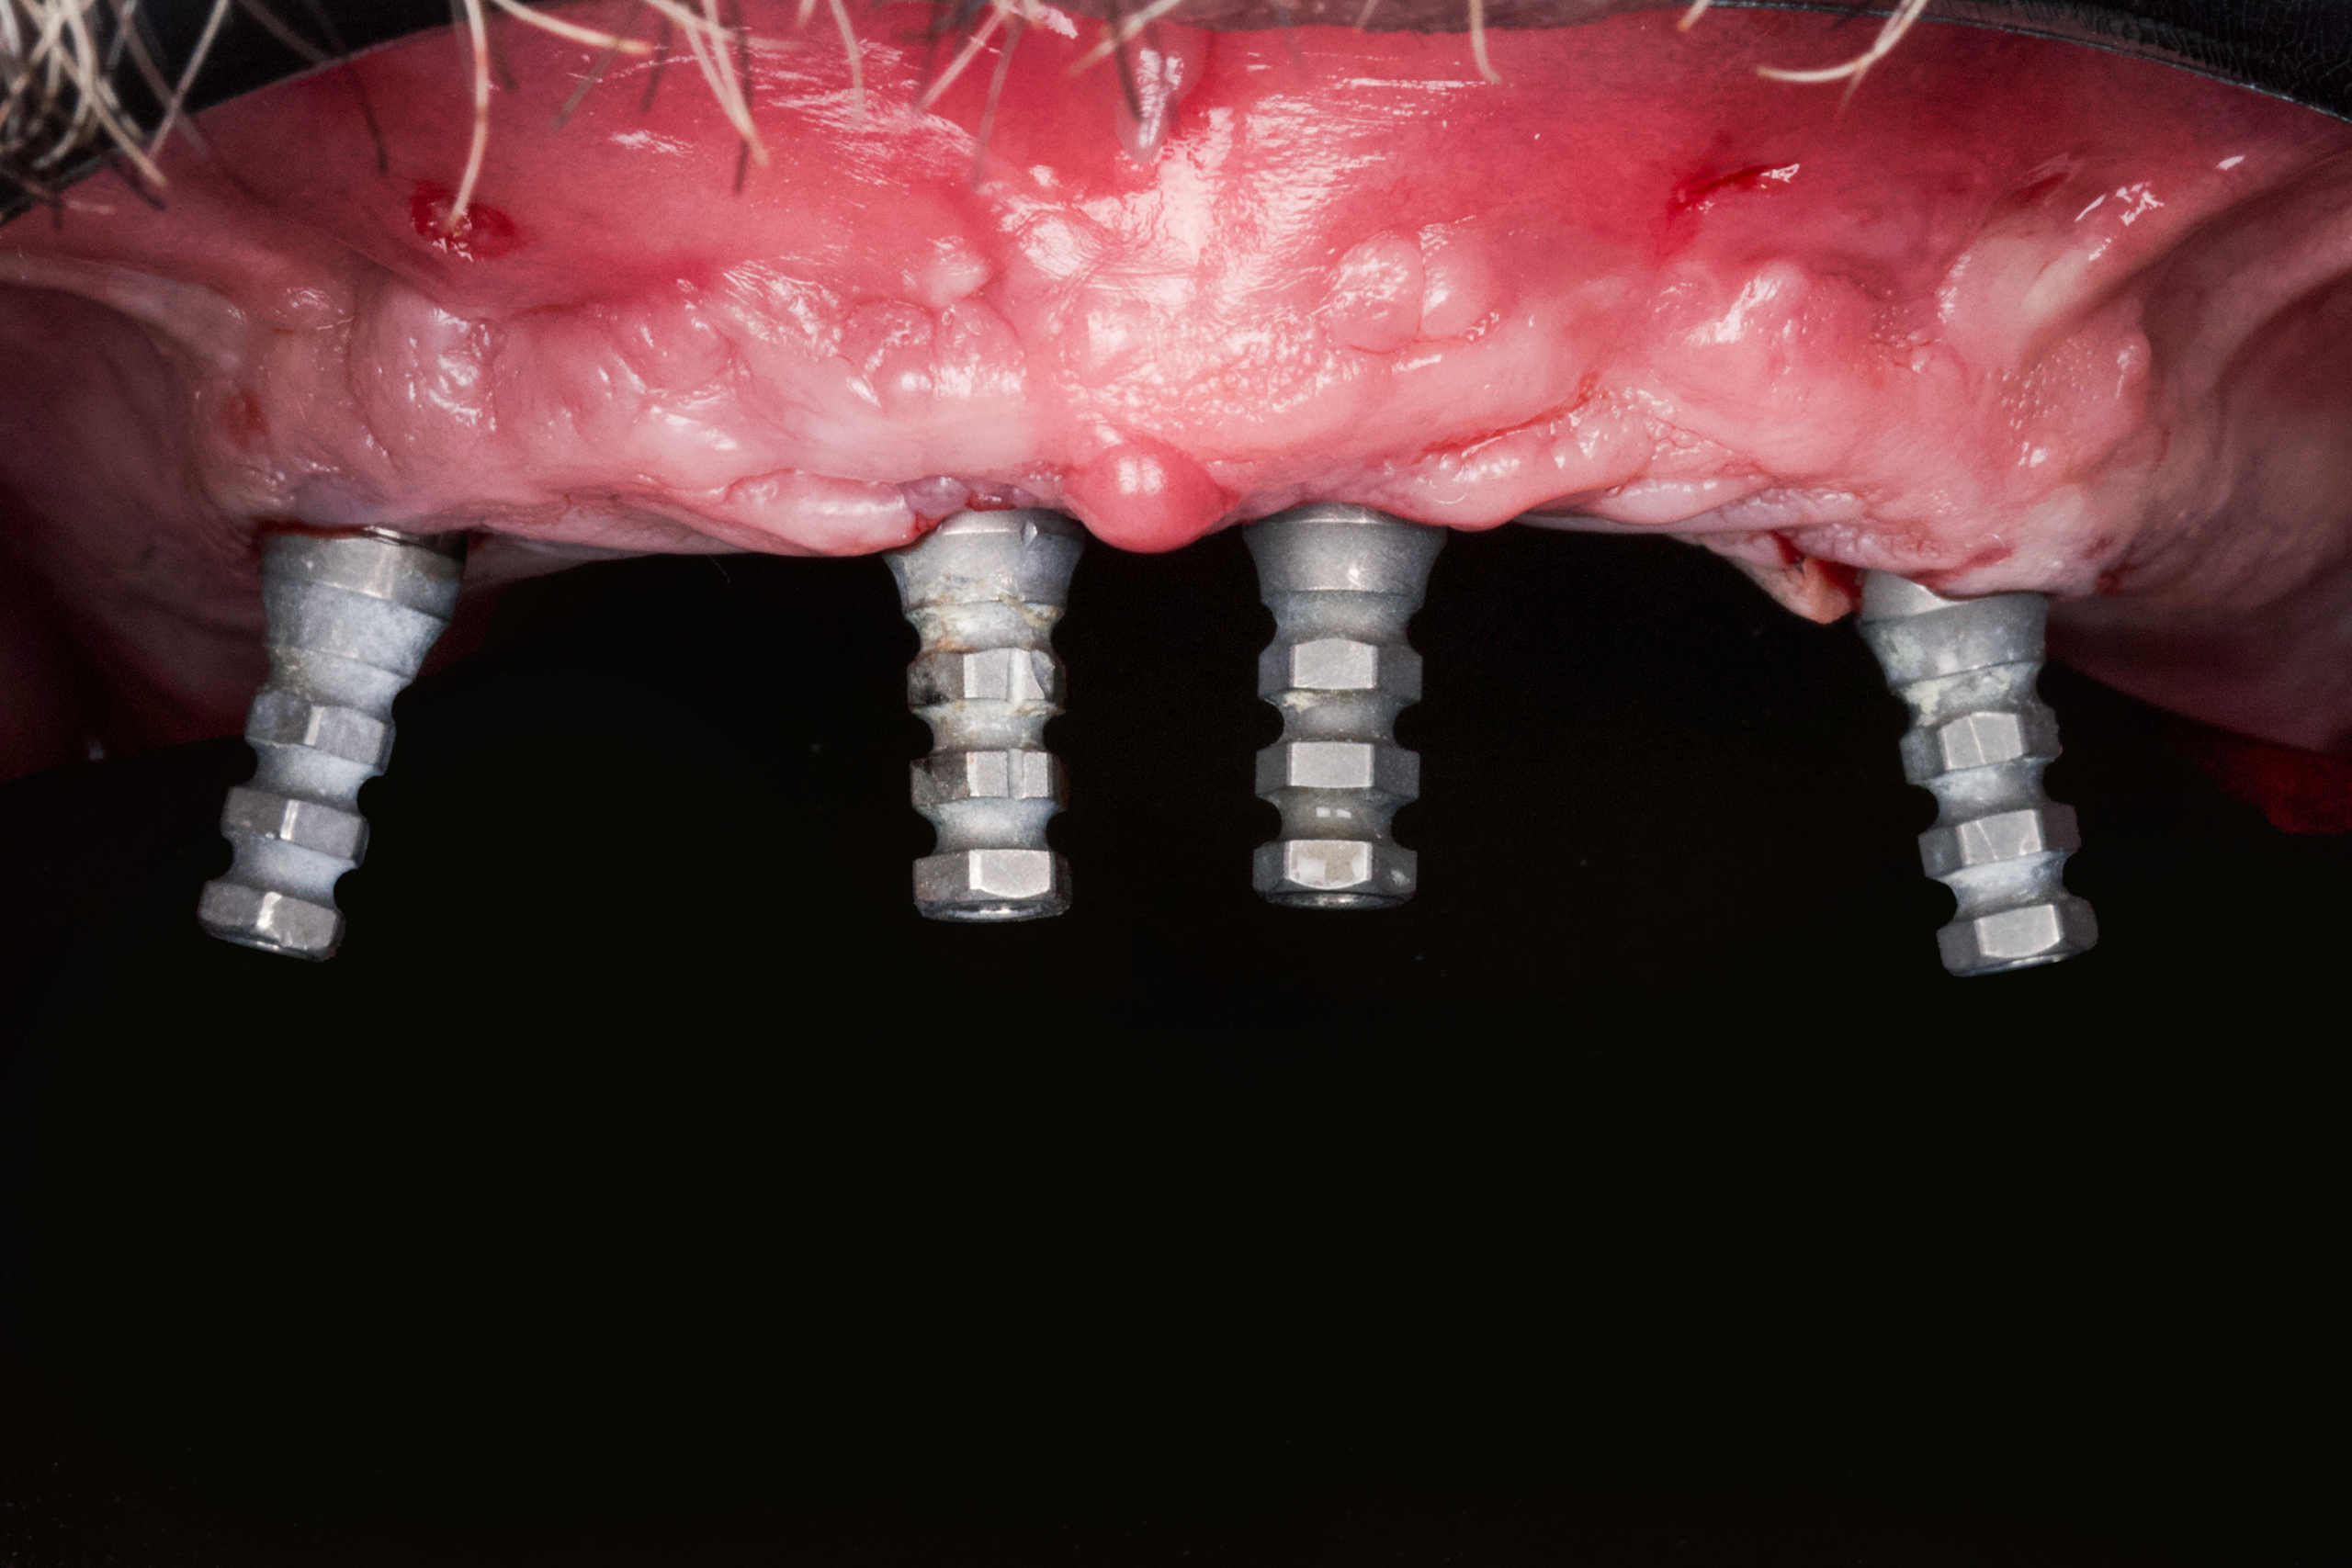

Day 2 — Surgical Phase

- Removal of all improperly placed implants

- Placement of four strategically positioned implants (All-on-4)

- Guided surgery ensured optimal distribution, angulation, and stability